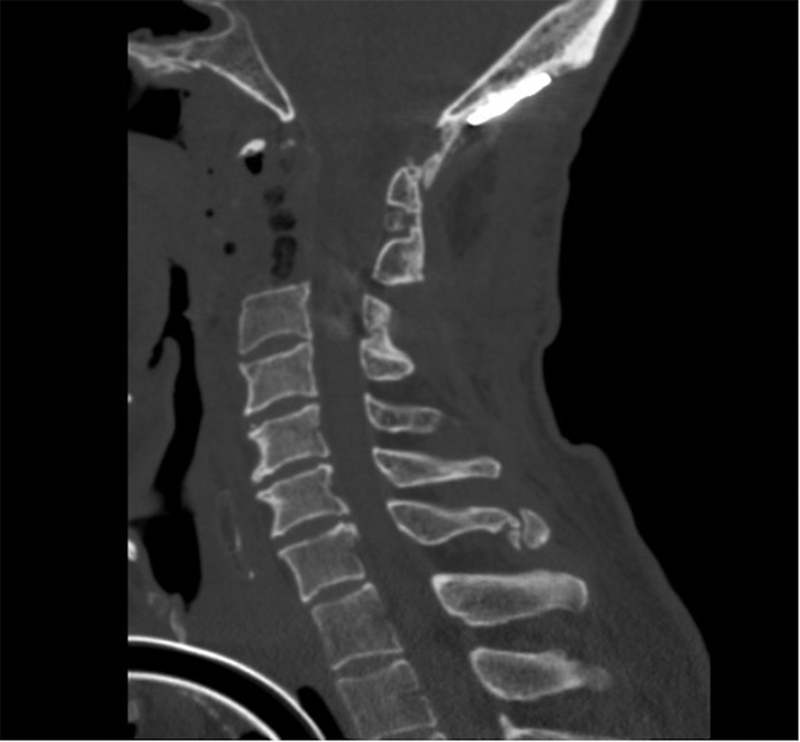

背景:脊索瘤是组织学上良性但局部侵袭性的肿瘤,易复发。我们的病例强调了在接受脊索瘤切除术的患者中长期警惕的重要性。病例报告我们报告一例47岁男性颈脊索瘤患者,在左侧锁骨上区、右侧二头肌近端和左侧下颌下区发生多发性肌肉骨骼异位复发,原发肿瘤部位无复发。原发性肿瘤切除是通过手术、辅助放射治疗和伊马替尼的联合治疗实现的。所有复发均成功切除,病理证实为异位脊索瘤。宫颈脊索瘤异位复发是罕见的,肺是最常见的远处扩散部位。骨骼肌脊索瘤复发尤其罕见,文献中仅报道了10例。脊索瘤患者远处转移的一种可能的机制表明,肿瘤细胞通过细胞因子释放、血管舒张和切除过程中引起的微创伤的结合而逃离手术道。结论颈椎脊索瘤伴骨骼肌异位复发的文献尚未见报道。颅底外科医生在没有局部复发的情况下,应注意脊索瘤异位复发的现象。

Background  Chordomas are histologically benign but locally aggressive tumors with a high propensity to recur. Our case highlights the importance of long-term vigilance in patients who have undergone chordoma resection. Case Report  We report the case of a 47-year-old man with a cervical chordoma who developed multiple musculoskeletal ectopic recurrences in the left supraclavicular region, the proximal right bicep, and the left submandibular region without recurrence in the primary tumor site. Primary tumor resection was achieved via a combination of surgery, adjuvant radiation therapy, and imatinib. All recurrences were successfully resected and confirmed via pathology to be ectopic chordoma. Discussion  Ectopic recurrence of cervical chordoma is rare and lung is the most common site of distant spread. Chordoma recurrence in skeletal muscle is particularly rare, with only 10 cases described in the literature. A plausible mechanism of distant metastatic disease in chordoma patients suggests that tumor cells escape the surgical tract via a combination of cytokine release, vasodilation, and microtrauma induced during resection. Conclusion  Cervical chordoma with ectopic recurrence in skeletal muscle has not been previously described in the literature. Skull base surgeons should be aware of the phenomenon of chordoma ectopic recurrence in the absence of local recurrence.